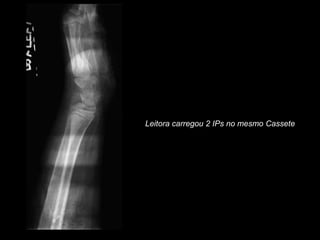

Leitora carregou 2 IPs no mesmo Cassete

Leitora carregou 2IPs no mesmo Cassete